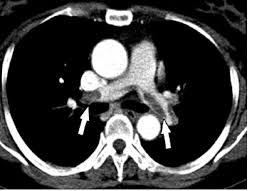

We’ve seen before that thrombolysis for intermediate PE (‘sub-massive’ with struggling right heart) doesn’t seem to save lives in the short term. PEITHO confirms that but there’s no long term data (cf MOPETT).